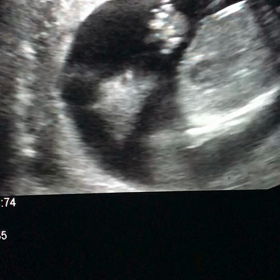

• エコー写真 6w5dの画像

エコー写真 6w5d